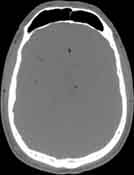

Visible Human male: Sectio transversalis 1074

CT